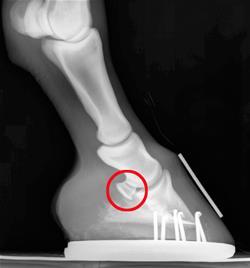

Navicular Syndrome

At the April 7 Veterinary Voices Seminar, Dan Burba, DVM, DACVS, professor of equine

surgery at OSU's Veterinary Medical Hospital, talked about navicular syndrome.